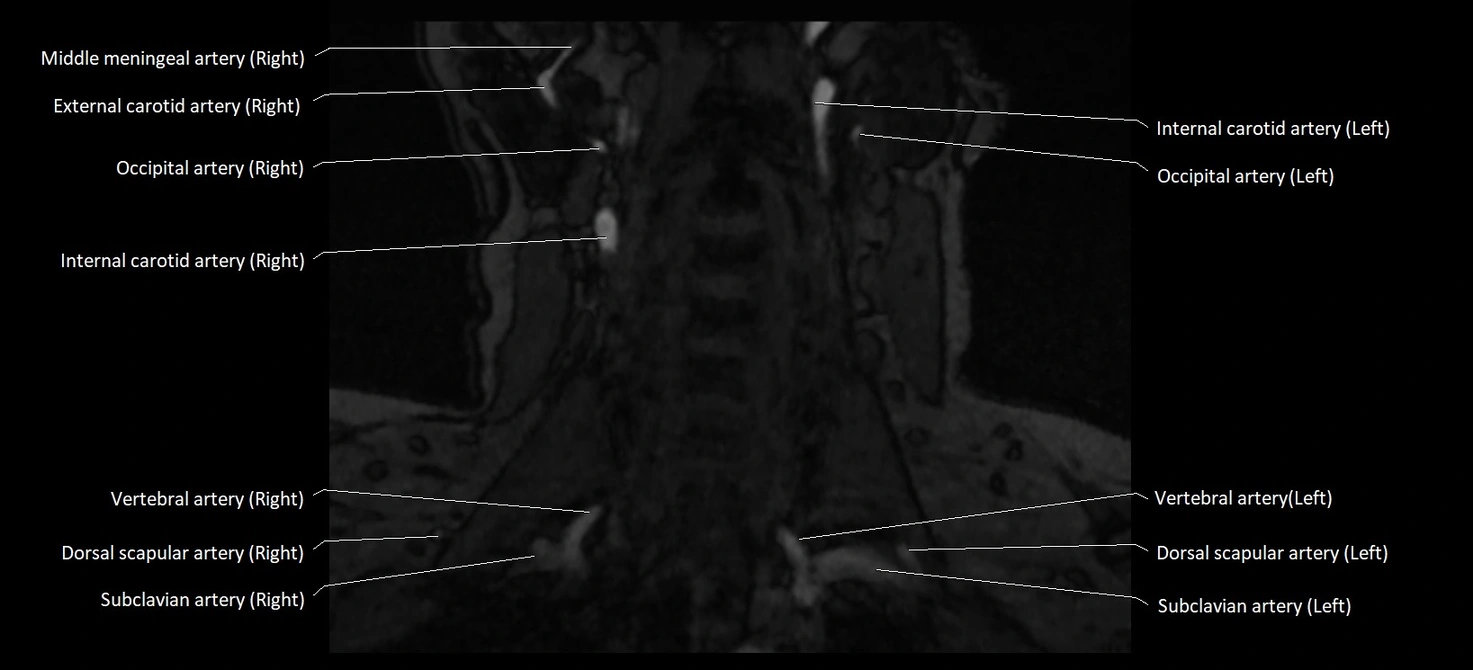

MRI images

image